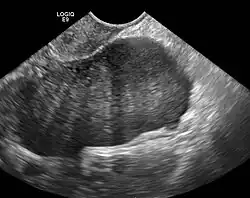

Diagnosis

Diagnosis is usually made by ultrasonography showing a solid ovarian lesion, or, on some occasions, mixed tumors with solid and cystic components.[1] Computed tomography and magnetic resonance imaging can also be used to diagnose fibromas. In a series of 16 patients, 5 (28%) showed elevated levels of CA-125.[1] Histopathology demonstrates spindle-shaped fibroblastic cells and abundant collagen.[3]